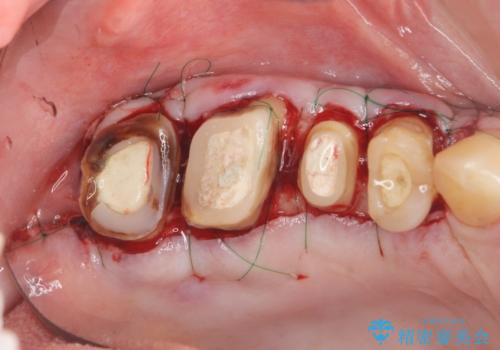

根管治療・歯周外科を行い歯を残した、複合的虫歯治療

クラウンの製作スペースの付属 →歯周外科によるスペースの確保

機能の回復・再感染の予防 →精密なジルコニアクラウンの作製

一つ一つの工程を丁寧に行うことで、根尖病変の改善傾向も見られ、安定した歯周環境を整えることができました。